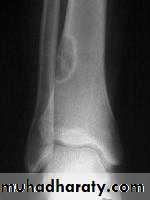

Painless lump on outer or inner table of skullEnchondroma

More in tubular bones of handAccidentally or pain / pathologic #

XR : lytic lesion + flecks of calcification

Malignant risk : 2%

Rx : curettage + bone graftPicture 4. Frontal radiograph of the right thigh demonstrates coarse calcifications in the distal femur.